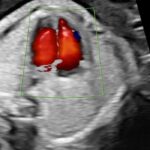

• Ecocardiografía Fetal (Semanas 24-28): Un estudio especializado del corazón fetal para descartar cardiopatías congénitas, especialmente en embarazos de alto riesgo.